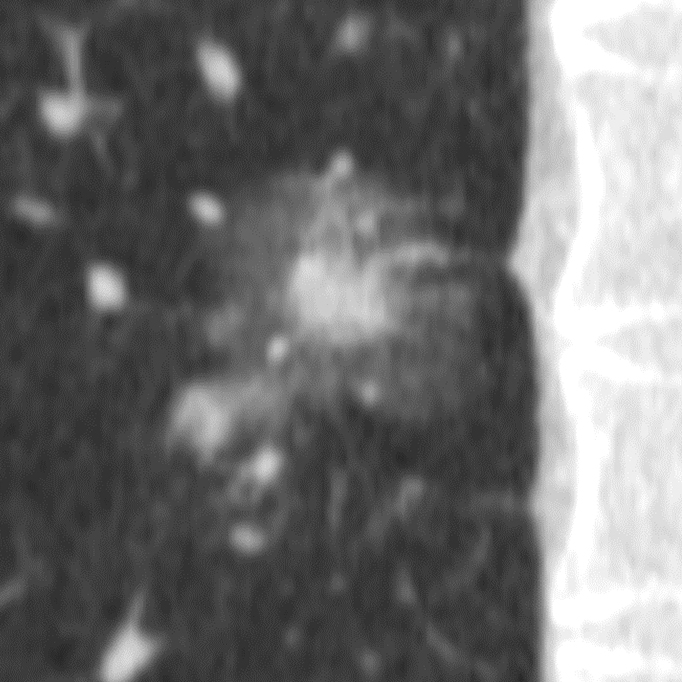

Порівняння звичайної роздільної здатності з ультрависокою роздільною здатністю (УРЗ)²

КТ з ультрависокою роздільною здатністю 0,25 мм ³